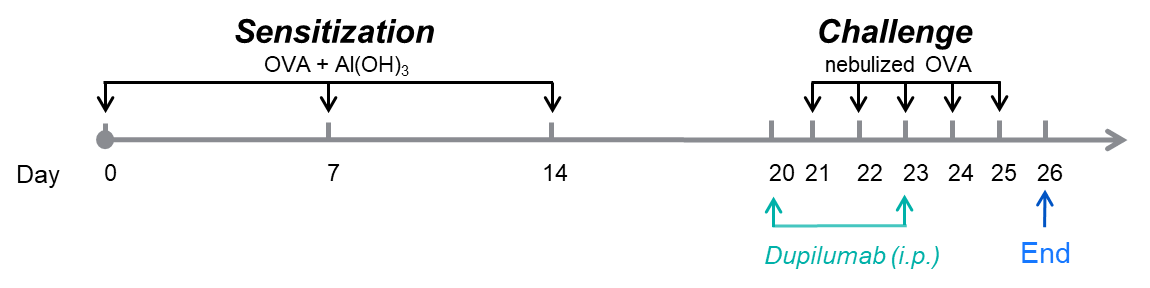

Airway responses following the exposure to increasing doses of methacholine (MCh) were measured for each mouse 24h after the final allergen or PBS exposure using the whole-body plethysmography. The y-axis represents the Penh absolute value. Increasing doses of methacholine were administered by aerosols.

B-hIL4/hIL4RA mice (C57BL/6)

B-hIL4/hIL4RA mice (BaIb/c)